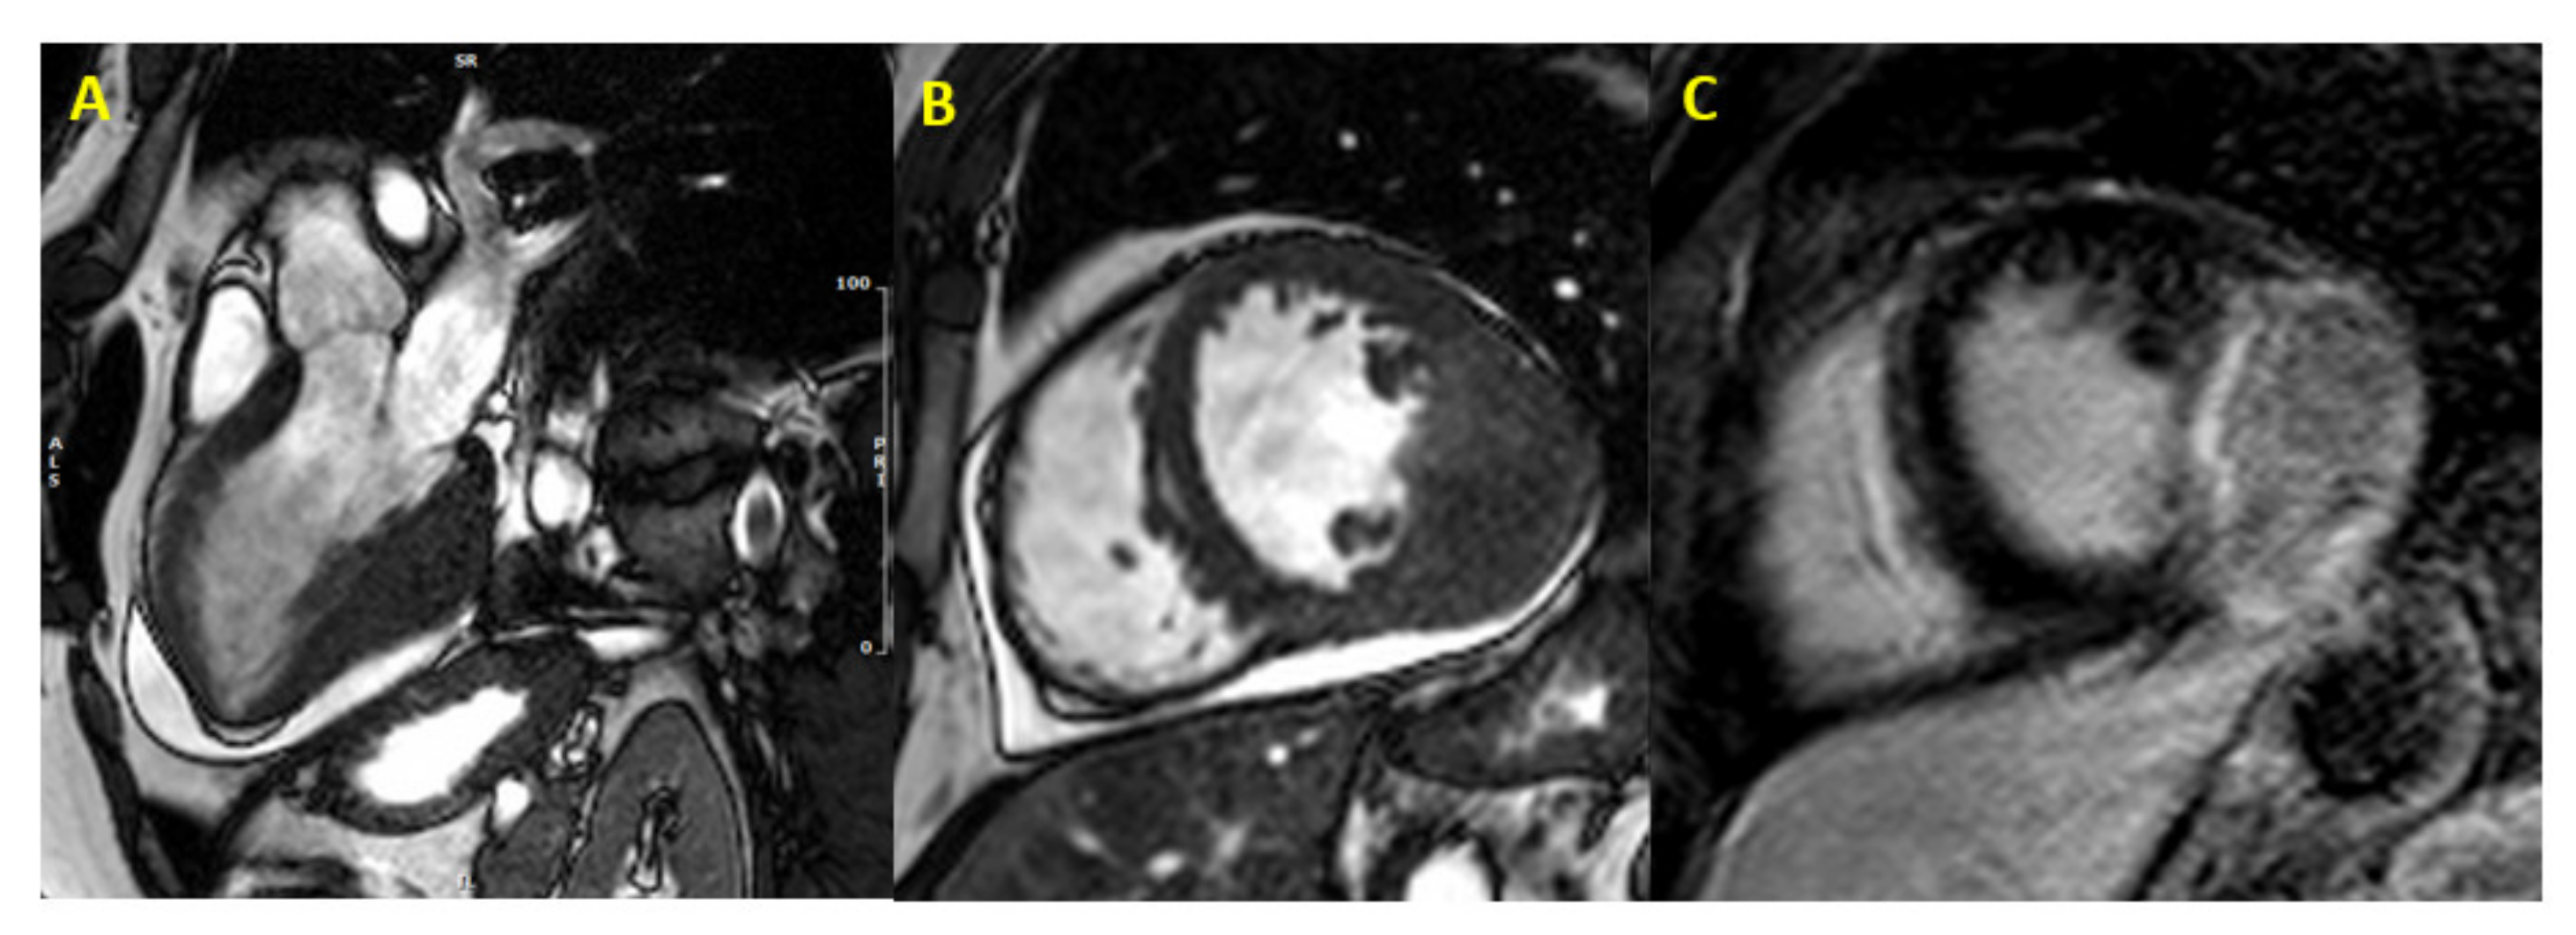

Figure 2.

Cardiac fibroma at CMR. Focal myocardial thickening of mid-basal infero-lateral wall, with isointense signal in basal SSFP sequences, mimicking HCM (Panel (A,B)). Heterogeneous LGE with a capsulated appearance of the focal hypertrophy suggesting cardiac fibroma (Panel (C)). (CMR = cardiac magnetic resonance; SSFP = steady-state free precession; HCM = hypertrophic cardiomyopathy; LGE = late gadolinium enhancement).